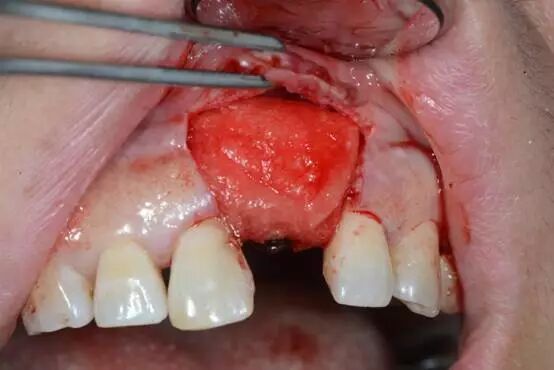

4.軟組織修復(fù)型材料在附著齦增厚術(shù)的應(yīng)用

軟組織修復(fù)型附著齦增厚術(shù)的應(yīng)用

牙周治療、拔牙后唇側(cè)

鄂側(cè)

骨缺損區(qū)域

使用鈦釘增加垂直骨高度

植骨并覆蓋GBR膜

二期植入種植體

覆蓋軟組織修復(fù)膜

5.0線縫合 唇側(cè)

術(shù)后四周? 顎側(cè)

唇側(cè)